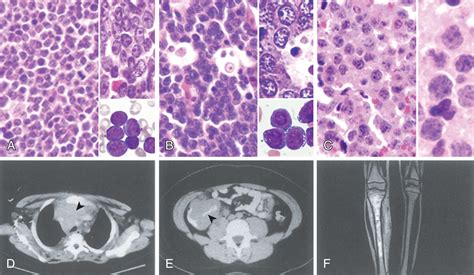

• Hodgkin Lymphoma: Characterized by the presence of specific abnormal cells known as Reed-Sternberg cells.

• Non-Hodgkin Lymphoma (NHL): A broader category that includes various subtypes, which generally grow more rapidly than Hodgkin lymphoma and behave differently.

Biopsy Removing a sample of the lymph node tissue for microscopic examination.

Imaging Scans (CT, PET, MRI) Creating detailed pictures to determine the location and size of tumors.

Bone Marrow Aspiration Checking if cancer cells have spread to the bone marrow.